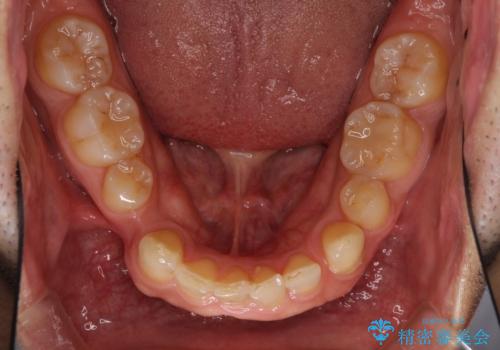

- 上下前歯のデコボコと下顎小臼歯の欠損によるスペースを気にして来院された患者様です。

下顎は左右1本ずつ小臼歯が欠損しており、右側にはやや大きな欠損がありました。

欠損により下顎歯列は相対的に小さく、上顎に深く咬みこんでしまうディープバイトとなっていました。

インビザラインによる治療を希望されたため、左側のスペースは閉じ、右側はスペースをより拡大し、インプラント補綴を行うこととしました。

咬合力が強く、インビザラインのみではディープバイトを改善することができず、半年間ほどワイヤー装置による矯正治療を行いました。

インプラントの埋入は矯正治療中に行い、矯正治療後はインプラント上補綴および、前歯のセラミック治療を行いました。